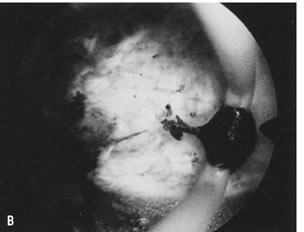

Fig. 21. Hysterosalpingogram shows an occupying lesion distorting the uterine cavity symmetry.

Fig. 22. Hysteroscopic view of pedunculated submucous myoma.